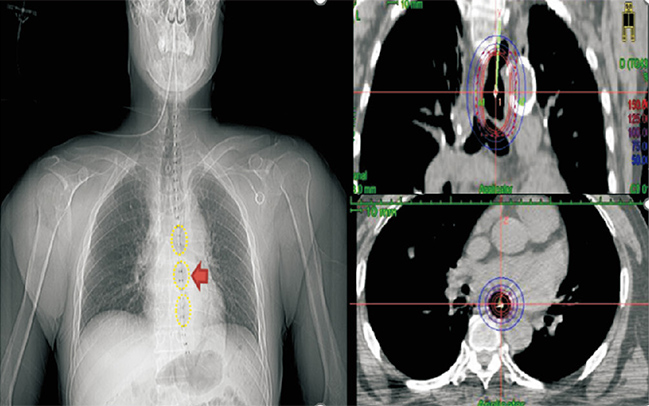

圖說:「近接治療」是屬於精準放射治療的一種,透過導管將放射性物質運送至腫瘤旁照射,適用於局部殘餘的病灶,或是用來減少腫瘤體積,

使病患可以進食。